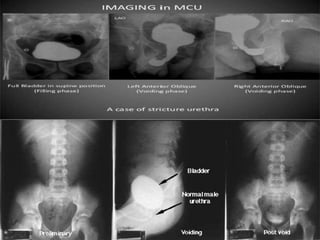

Role of urethrography in stricture

• Accurately delineates the anatomy of urethra.

• Location, number and extent of the strictures are

very well displayed

• Delineation of the bladder neck and urethra is best

achieved on the MCU in the oblique projection.

• Secondary changes in the bladder.

• Todemonstrate the VUR

• Visualisation of any associated fistulas.